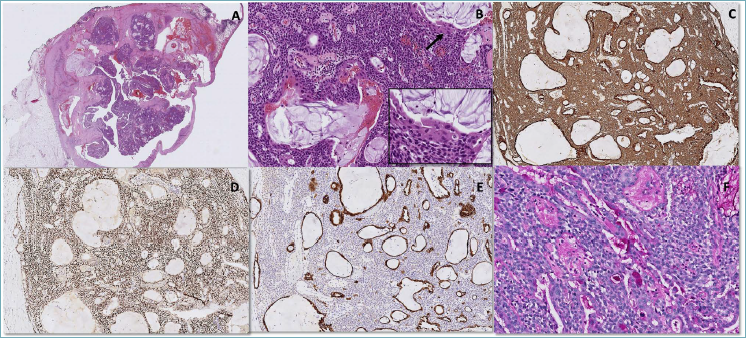

Microscopic examination demonstrated a well-circumscribed tumor mainly composed of intermediate cells intermingled with goblet mucus-secreting cells, both arranged in solid and mucin-filled cystic spaces (Fig. 2 A, B), along with the occasional presence of squamous cells (Fig. 2B). Additional key histologic features included a very low mitotic index and an absence of nuclear pleomorphism.

On immunohistochemistry, the intermediate cells were immunoreactive for CKAE1/AE3, p40 and p63 and negative for CK7 and CEA, whereas the mucous cells resulted partially positive for CKAE1/AE3, CK7, CEA (luminal pattern) with variable staining intensity (Fig. 2 C, D, E). Squamous cells showed strong expression of both p40 and p63 markers. Stains for napsin A, TTF1, chromogranin, synaptophysin, INSM1, S100, CD117, SALL4, calretinin, WT1, CD34, CD30 and CD5 were negative. The Ki-67 index was 7%. Periodic acid-Schiff (PAS)-diastase staining highlighted mucinous secretion in goblet cells (Fig. 2F). Bioactive thymic remnants composed of a characteristic mixture of immature T cells (CD3+ and TdT+) and reticular epithelial cells (CKAE1/AE3 +, p40+) were present in the surrounding tissue.

The percentage of cystic spaces (> 20%), absence of necrosis and nuclear atypia, and low mitotic index led us to make the diagnosis of low-grade TMEC.

Figure 2. A (H&E; 2x): microscopic examination showed a well-circumscribed lesion composed of combined cystic, solid areas and extracellular pools of mucin in the background of a dense fibrous stroma. B (H&E; 10x): microscopic examination showed a triphasic tumor composed of epidermoid cells (arrow) intermingled with mucous (round) cells lining cystic cavities and intermediate cells. The immunohistochemical profile (Immunostains; 10x) exhibited positive staining for CKAE1/AE3 (C) outlining the epithelial nature of the three components; positive staining for CK7 (D) in the cells lining cystic spaces and positive staining for p63 (E) in the intermediate cells was detected. The presence of mucoid cells (F) was demonstrated by PAS-diastase staining (histochemical stain; 20x).